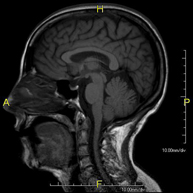

- Brain MRI (cranial)

This non-invasive diagnostic procedure uses an electromagnetic field and radio waves (from a transmitter and receiver) to acquire high-definition anatomical images of the brain. It is a radiation-free procedure. Indicated for: vascular problems, memory loss, epilepsy, headache, malformations, suspected tumour, meningitis.